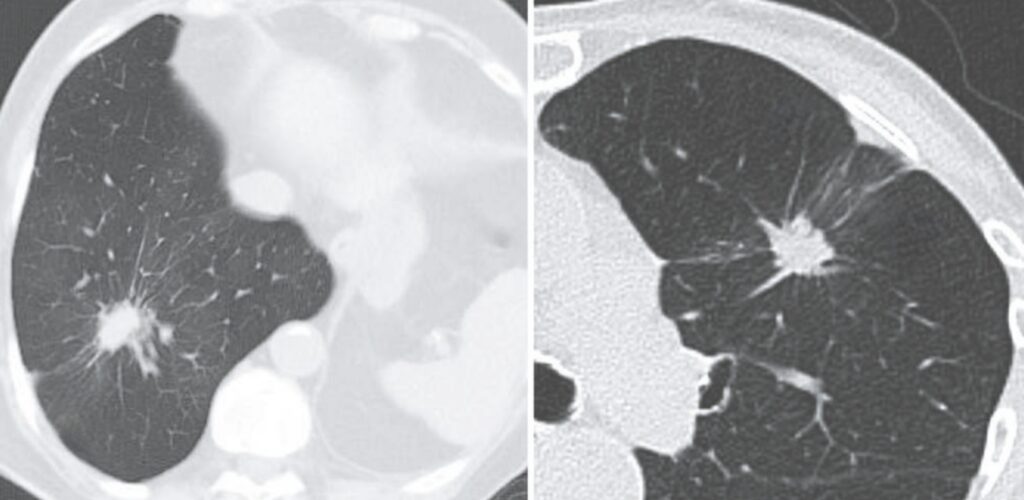

The Rigler Notch Sign refers to a notched or umbilicated indentation along the border of a pulmonary mass, seen on radiographic imaging. It is traditionally interpreted as suggestive of malignancy, particularly bronchial carcinoma, though it can occur in benign conditions such as granulomatous disease or bronchial adenoma. The sign is most reliably observed on body-section roentgenograms and CT imaging.

- Location: Typically along the medial or inferior margin of a spheroidal lung mass.

- Appearance: A sharp, focal indentation or groove on an otherwise smooth mass border.

- Interpretation: May represent a feeding vessel, retracted bronchus, or vascular hilus-like configuration within the tumour mass.

- “Navel-like retraction” seen on CT, associated with tumors overgrowing adjacent vessels.

- Best demonstrated: On CT chest with contrast, especially thin-slice axial reconstructions.